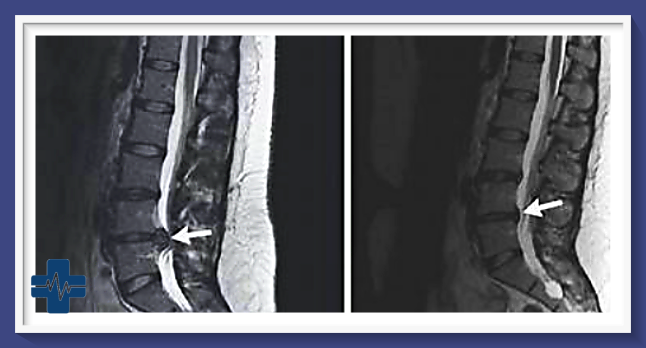

허리디스크는 척추뼈 사이에 위치한 추간판이 파열되어 그 안의 수핵이 밖으로 튀어나오는 질환입니다. 특히 갑작스럽게 디스크가 터지는 급성 허리디스크의 경우 극심한 통증과 함께 일상생활에 큰 지장을 초래할 수 있어 주의가 필요합니다.

급성 허리디스크가 발생하면 허리에 심한 통증이 나타나는데, 마치 칼로 베는 듯한 날카로운 통증부터 쥐어짜는 듯한 둔통까지 다양합니다. 통증은 가만히 있어도 지속되며 특정 자세를 취하면 더욱 심해집니다. 통증으로 인해 허리를 구부리기 어렵고 똑바로 설 수 없게 됩니다.

통증은 허리에 국한되지 않고 둔부, 대퇴부, 종아리, 발끝까지 뻗치는 방사통 형태로 나타나기도 합니다. 이는 파열된 디스크가 신경을 누르기 때문입니다. 신경이 눌리면서 저린 느낌, 감각 저하, 근력 약화 등의 신경학적 증상이 동반되기도 합니다.

수술은 심한 신경학적 증상이 동반되거나, 충분한 보존적 치료에도 호전이 없는 경우 고려됩니다. 수술로 파열된 디스크를 제거하면 눌렸던 신경이 감압되어 즉각적인 통증 완화 효과를 얻을 수 있습니다.